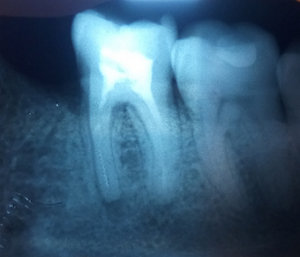

У меня зуб болит. Я его лечила 3 года назад. Мне поставили штифт в декабре 2015, он опять заболел, сделали снимок, оказалось, что он был плохо пролечен. Сняли пломбу, смогли пройти только один канал, во втором канале материал, третий мне врач не смог пройти (инструмент упирался в десну). Тогда еще врач сказал, что этот зуб только удалять, я не согласилась на удаление и мне его просто перекрыли пломбой, теперь опять побаливает.

В зубе имеется перфорация, к сожалению, такой зуб спасти и сохранить невозможно.